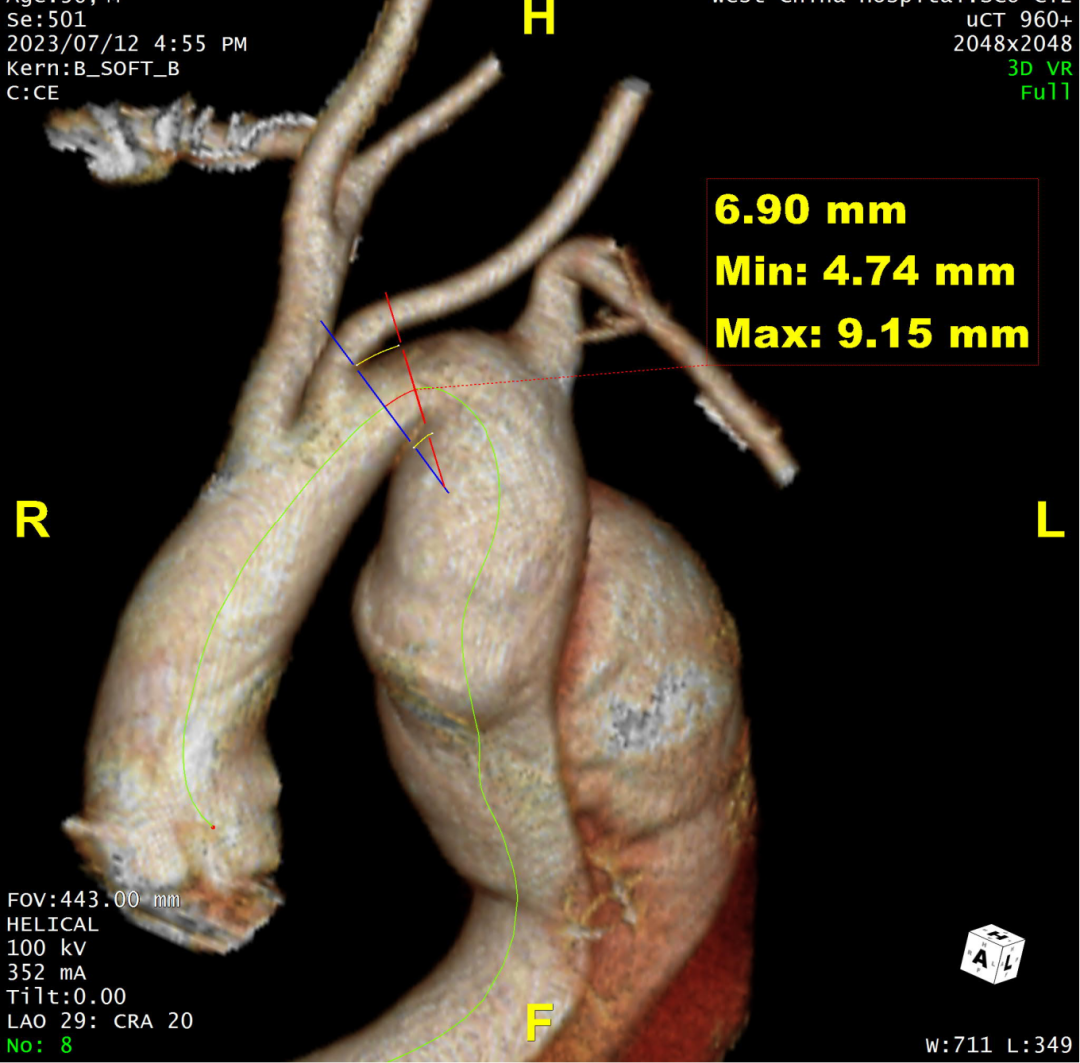

术前CTA评估与测量

术前CTA提示主动脉夹层(Stanford B型,Debake llI型),主动脉弓及降主动脉瘤样扩张,累及左锁骨下动脉起始段,管径最粗约7.4cm,夹层初破口位于降主动脉起始段,向下累及至腹主动脉(约平胸12椎体水平),真腔小,假腔大,腹腔干发自混合腔,肠系膜上动脉、下动脉,双肾动脉均起自真腔,双肾灌注未见差异。

术前三维重建

术前CTA详解:

病例特点

1. 弓型陡峭,成角;

2. 自左颈总后缘小弯侧锚定区不足1cm;

3. 巨大破口,约33mm,病变累及至腹腔干平面。